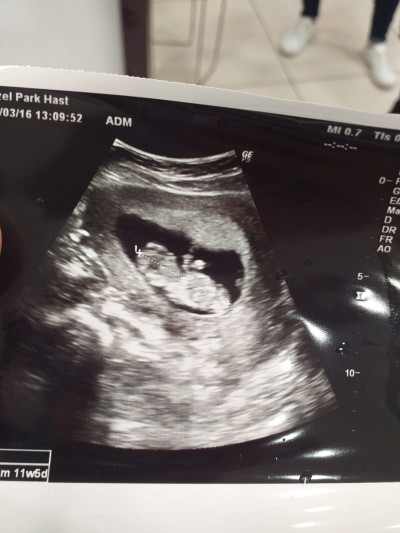

Kızlar merhaba doktorum kıza benziyor ama muallakta dedi 11+5 cinsiyet tahmini olanlar var mı tabi öncellike saglıklı olması ama ilk oldugu için heyecanlanıyorum

Gebelik haftası 11+5

Nubu paralel bu usg ye gore kiz canm

Benimde buna keseye göre kızdı ama oğlum olcak.. yani öyle birşey yok.16 haftayı bekle

Cinsiyet için çok erken.. banada 12+5de kız dendi özele gidiyorum ve doktorumda çok iyi.. bende ultrasonda gördüm bacak arası boştu.. 16. Haftada erkek dedi gayet net gördüm.. 16. Haftada tam oluşuyor cinsiyet canım.. biraz daha sabır kız diye şartlama kendini